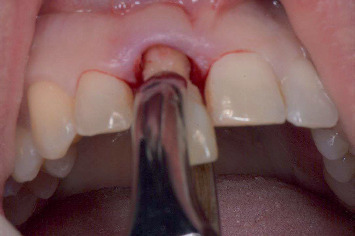

简介:当用种植体替换美学区单个牙齿时,对于大面积颊骨缺损的病例,保留牙槽嵴是必要的。假体驱动种植体放置在保留的脊上,随后立即进行患者特定的临时修复,可以通过数字治疗计划实现。数字化工作流程结合了口腔内光学扫描和锥形束计算机断层扫描,实现了三维临床和放射学解剖评估。此外,它通过计算机辅助手术和CAD/CAM钛基台的临时修复预制,促进了完全引导的种植体放置。材料与方法:对3例上颌美观区缺牙及颊骨缺损bbbb5 mm的患者行牙槽嵴保存术。四个月后,使用数字工作流程放置种植体,并使用患者特定的钛基台进行预制临时修复。3个月后进行了最终修复。在治疗前、临时修复后6周、最终修复后1个月和1年评估临床、美学、放射学和患者报告的结果。结果:3例患者在牙槽嵴保存后伤口愈合良好,种植体可按计划放置并临时修复。在最后的随访中,观察到健康的种植体周围组织,美观性好,患者满意度高。结论:三个报告的病例展示了数字工作流程在上颌美学区保留脊中使用预制修复体进行延迟种植体放置的潜力。

Introduction: When replacing a single tooth in the aesthetic zone with an implant, alveolar ridge preservation is necessary in cases with extensive buccal bone defects. Prosthetically driven implant placement in the preserved ridge, followed by an immediate patient-specific temporary restoration, can be achieved with digital treatment planning. A digital workflow incorporates intraoral optical scanning and cone beam computed tomography, enabling a three-dimensional clinical and radiographic anatomy assessment. Furthermore, it facilitates fully guided implant placement by means of computer-assisted surgery and the prefabrication of temporary restorations with a CAD/CAM titanium abutment. Materials and Methods: Three patients with a failing tooth in the maxillary aesthetic zone and a buccal bone defect > 5 mm underwent alveolar ridge preservation. Four months later, a digital workflow was used to place the implant, which was restored with a prefabricated temporary restoration with a patient-specific titanium abutment. The definitive restoration was placed 3 months later. Clinical, aesthetic, radiographic, and patient-reported outcomes were assessed before treatment, 6 weeks after temporary restoration, and 1 month and 1 year following definitive restoration. Results: In all three cases, wound healing after alveolar ridge preservation was uneventful, and the implants could be placed and restored with a temporary restoration, as planned. At the final follow-up, healthy peri-implant tissues were observed with good aesthetics and high patient satisfaction. Conclusion: The three reported cases demonstrate the potential of a digital workflow for delayed implant placement with provisionalization using prefabricated restorations in preserved ridges within the maxillary aesthetic zone.